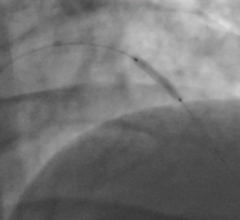

Cardiovascular Clinical Studies

This channel includes news and new technology innovations from cardiovascular clinical trials. These clinical studies include all cardiac subspecialties.